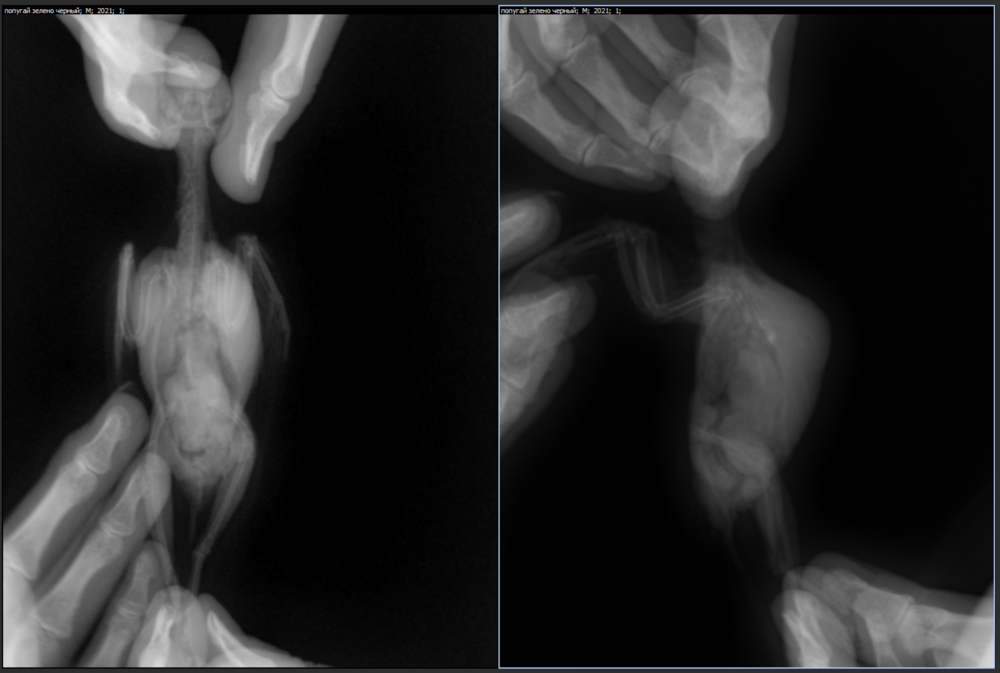

Вызвали доктора, сделали пункцию, шишки не было.Капала капли вигамокс. В течении 5 дней она снова начала рости, через 5 дней исчезла. через 3 дня после этого шишка снова появилась и начала рости, в итоге сейчас она того же размера как была до пункции .Сама птица прекрасно себя чувствует, активничает в меру возраста, подтеков из носа никаких.  Делала рентген птицам, врач прописал: офолосан 0,05 размешать с 0,9 воды и давать по 0,1 мл в день 3 недели; гепатовет кошачий 0,1 мл 1 раз в день 2 месяца. Даю уже 5 дней, пока никаких изменений.

Суть в том, что у них вроде как инфекция, но я совсем не понимаю отчего у него эта шишка.. На синусит не похоже вроде, на абсцесс тоже.. ничего похожего в интернете не нашла толком. Буду благодарна за помощь! (Рентген зеленого попугая, но есть и желтой, могу приложить, если надо. У нее в принципе тоже самое легкое тоже белее другого)

зеленый.png